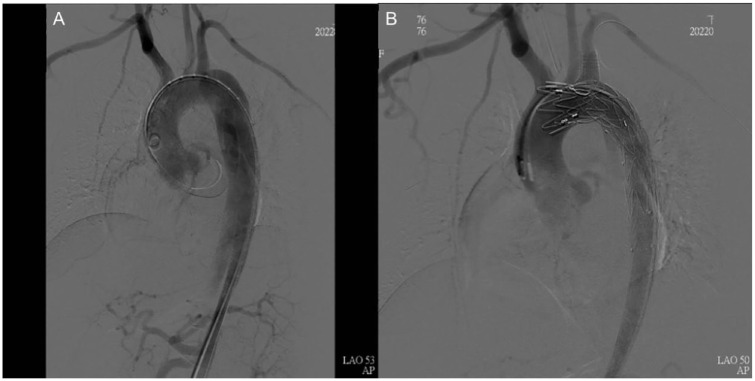

Case report: A case report involving a 33-year-old female with Stanford type B aortic dissection at 32 + 3 weeks gestational age highlights the importance of being alert to the symptoms and signs of this condition, particularly in patients with hypertension or a history of connective tissue disorders. The case report suggests a delivery first strategy followed by TEVAR procedure as the preferred approach for managing aortic dissection in pregnancy. This approach can alleviate pressure on the aorta, reduce the risk of rupture, and provide time for stabilization and preparation for the TEVAR procedure.